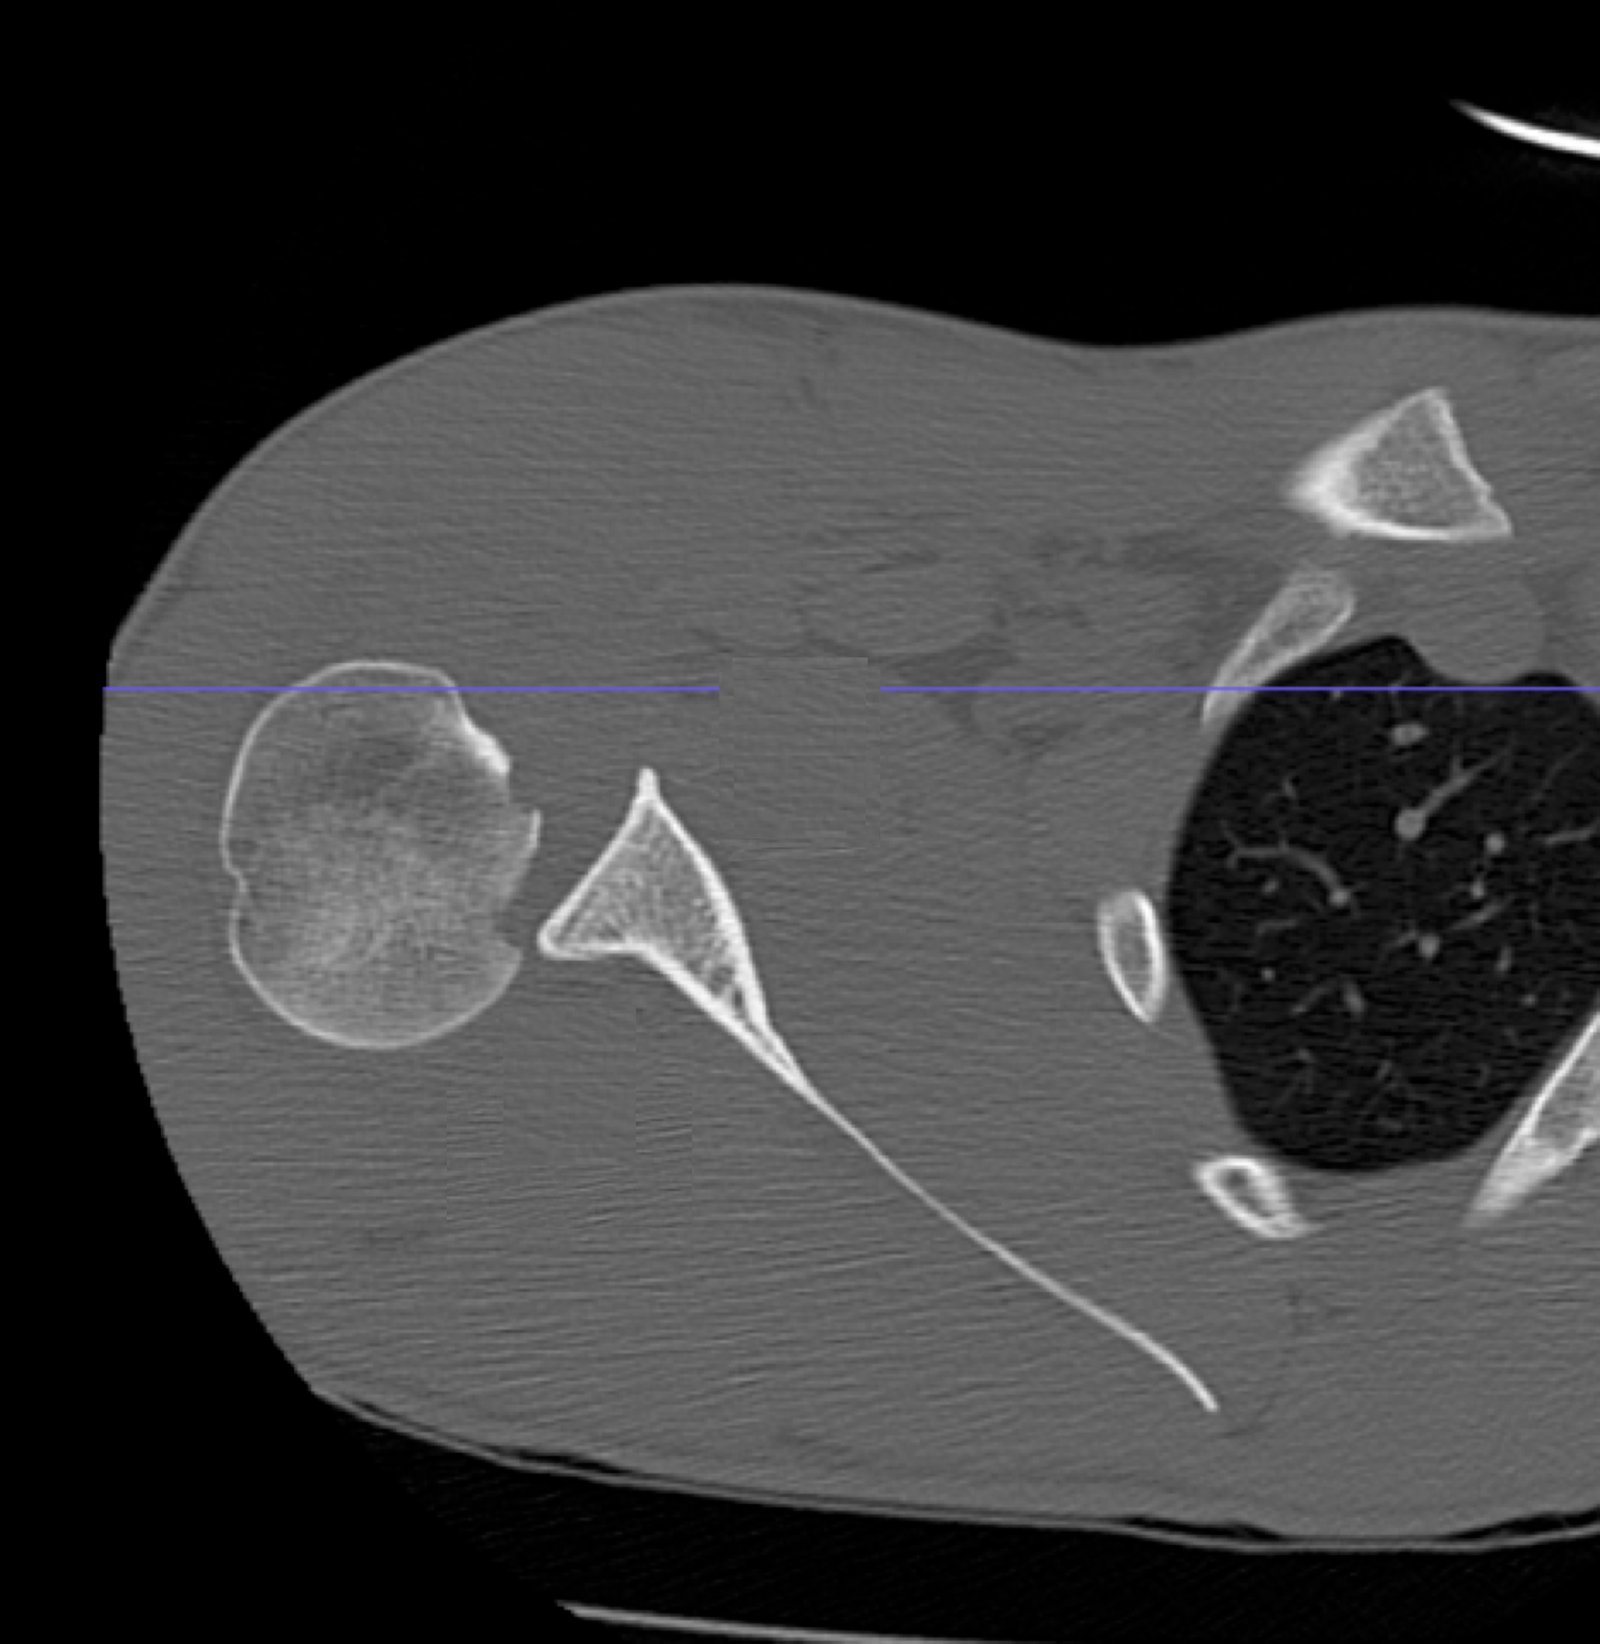

Posterior Shoulder Dislocation, CT. JETem 2017

Irreducible Traumatic Posterior Shoulder Dislocation